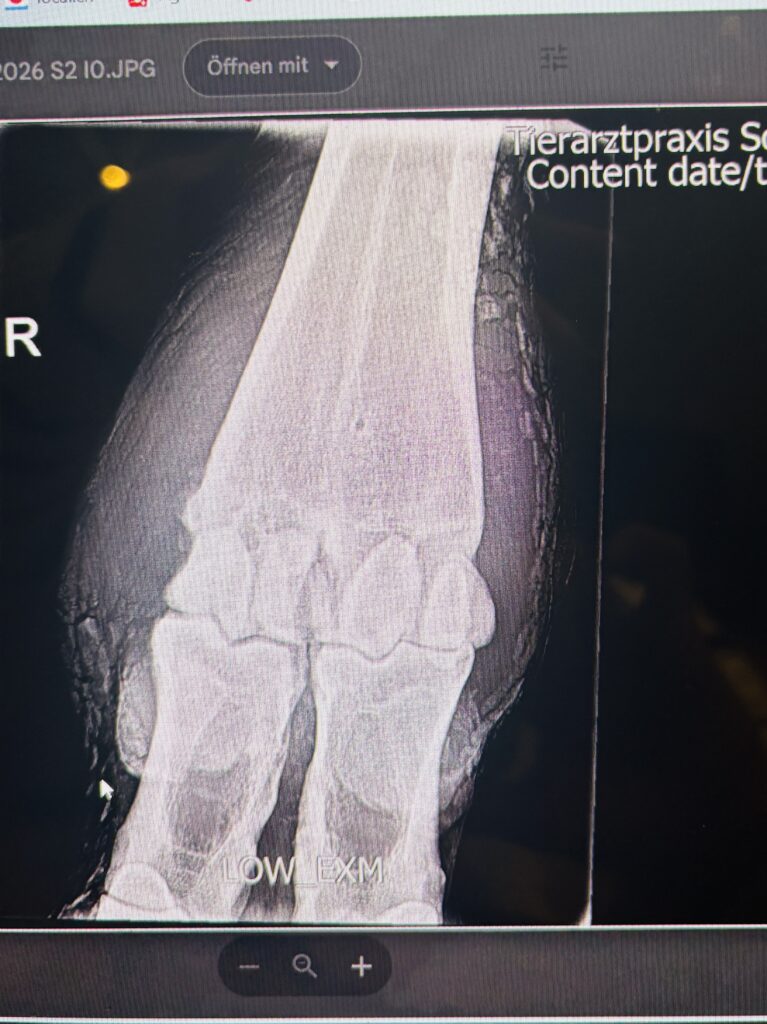

Eine Kuh, die trotz Behandlung nur langsam Fortschritte machte, erforderte eine genauere Abklärung. Mit unserem mobilen Röntgengerät für Nutztiere konnten wir die Situation direkt im Stall beurteilen – ohne zusätzlichen Transport und ohne zusätzlichen Stress für das Tier.

Gerade in solchen Momenten ist es entscheidend, möglichst rasch Klarheit zu gewinnen:

Besteht eine knöcherne Beteiligung? Wie ist die Prognose einzuschätzen? Und welche nächsten Schritte sind sinnvoll?

Die Möglichkeit, diese Fragen unmittelbar vor Ort zu klären, ist eine grosse Erleichterung – für die Kuh und für den Tierhalter.

Mobiles Röntgen bei Kühen im Stall gehört zu den Leistungen, die aktuell in unserer Region praktisch nicht angeboten werden.